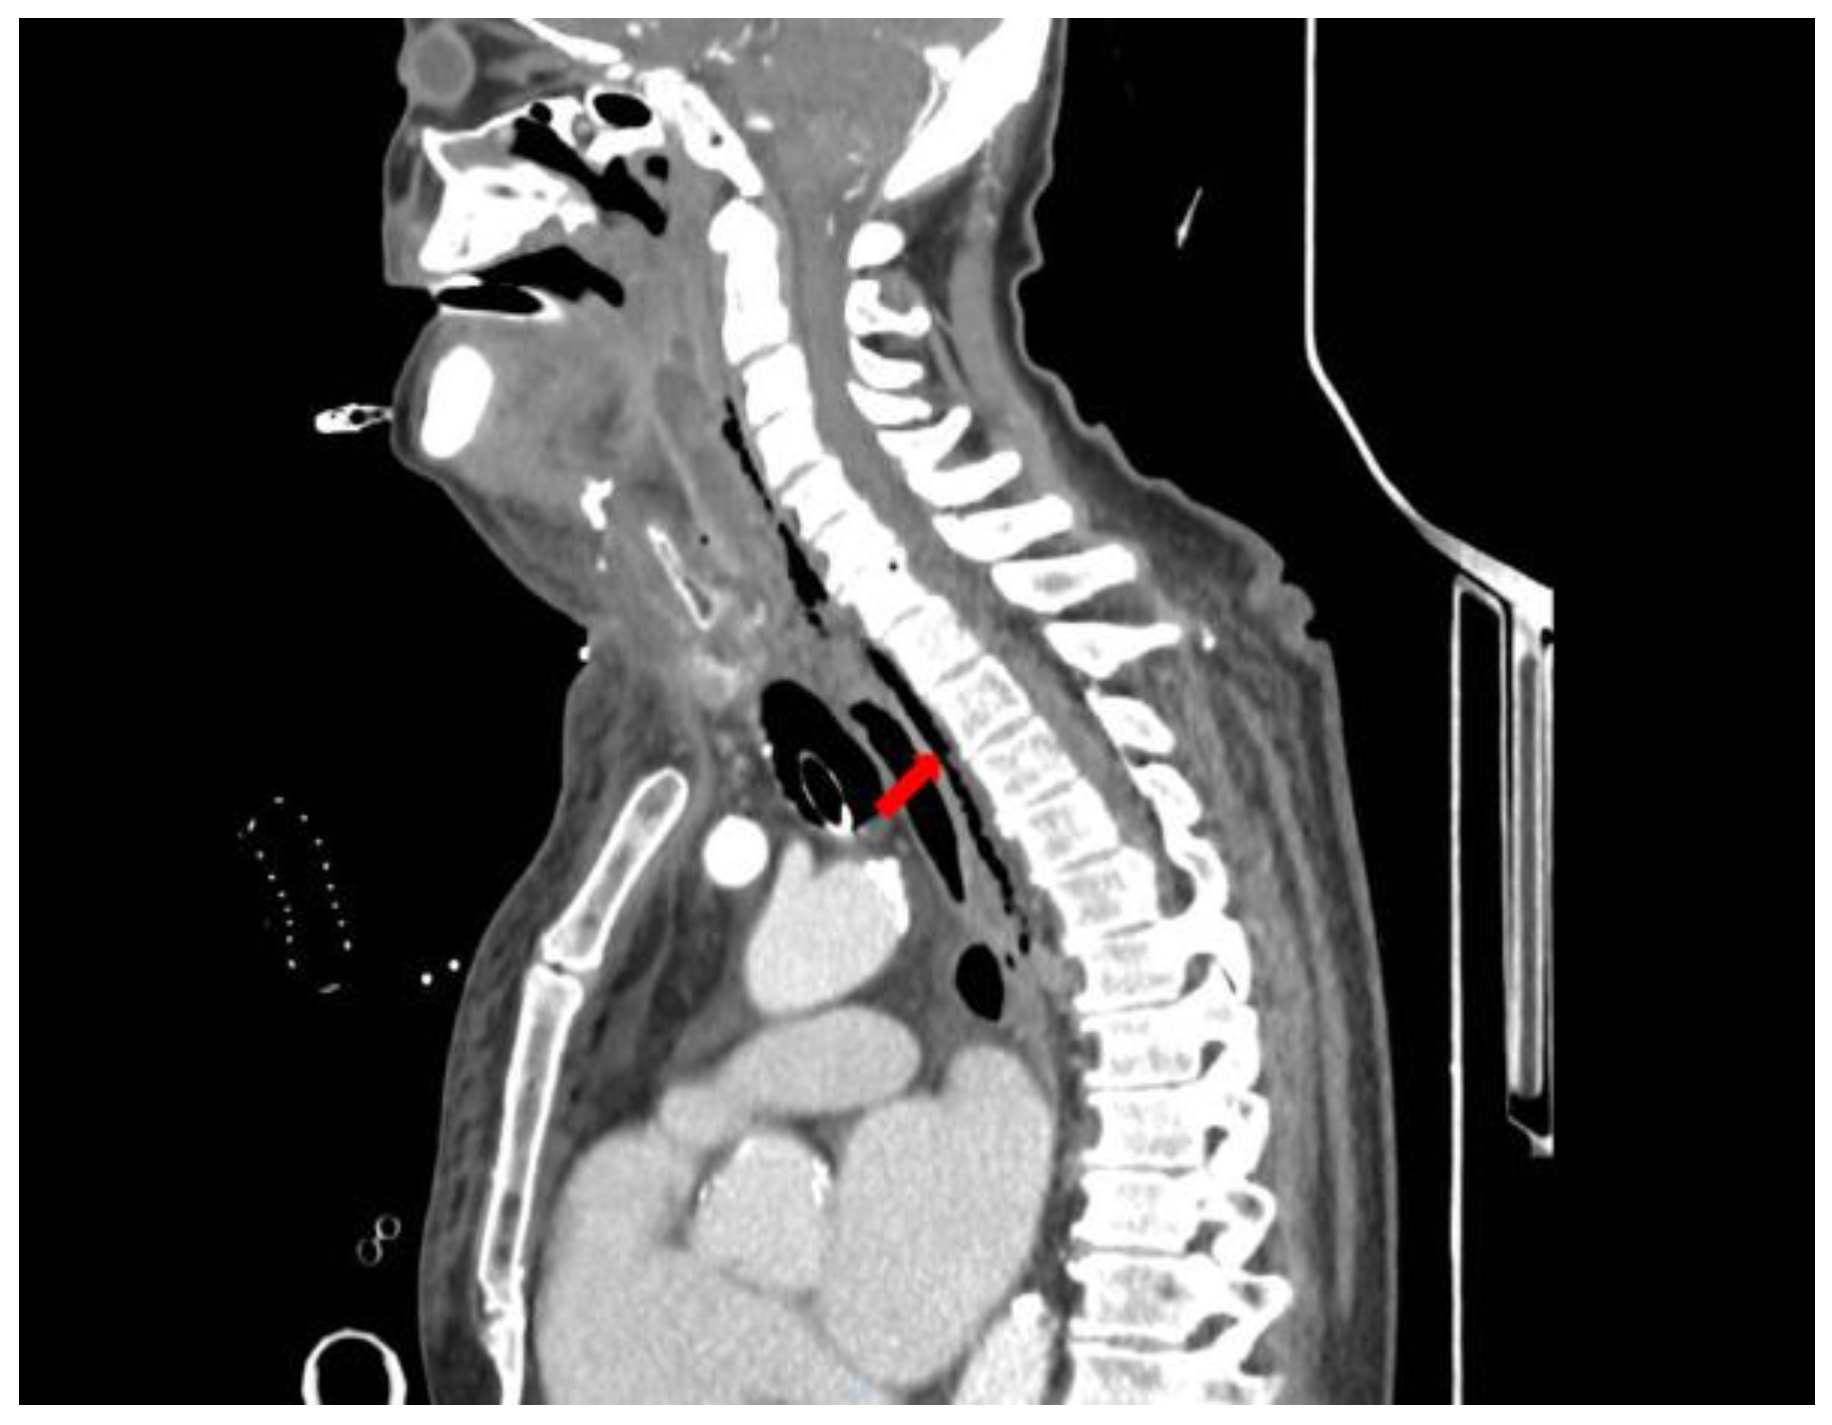

A CT scan of the head, neck, and chest with intravenous contrast, revealed a retrotonsillar fluid collection, with a maximum diameter of 10 cm, extended anteriorly to the right lobe of the thyroid gland (Figure 1). Air bubbles and minimal fluid were present from the right submandibular area to the lower mediastinum between the spine, the descending thoracic aorta, and the trachea (Figure 2).

Figure 1.

CT scan of head, neck, and chest with intravenous contrast material, shows a retropharyngeal collection (yellow arrow) and submandibular air bubbles (white arrow).